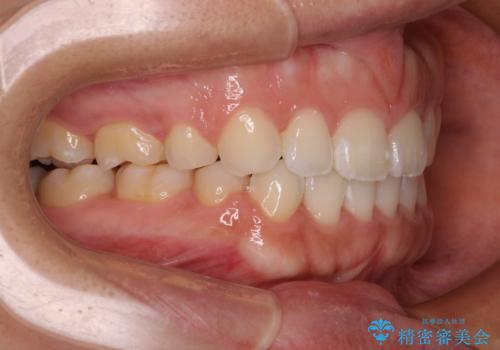

- 口が閉じにくさを気にして来院された患者様です。

上下の前歯が前方に突出していたため、上下左右の第一小臼歯4本を抜歯し、ワイヤー装置にて抜歯矯正を行うこととしました。

上下前歯部の被蓋関係を改善するの時間がかかり、3年間を要することとなりましたが、スッキリとした口元に仕上がりました。